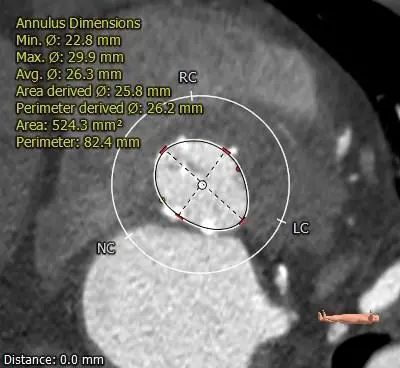

ANNULUS

2mm SUPRA ANNULUS

4mm SUPRA ANNULUS

6mm SUPRA ANNULUS

8mm SUPRA ANNULUS

10mm SUPRA ANNULUS

12mm SUPRA ANNULUS